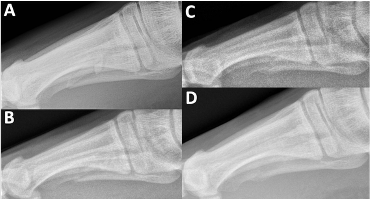

On examination, there was focal tenderness over the dorsal lateral forefoot without gross deformity, open wounds, or sensory deficits. Vascular status was grossly intact. Three views of non-weight-bearing radiographs revealed a mildly comminuted mid-diaphyseal fifth metatarsal fracture with a small angulated butterfly fragment (Figures 1A, 2A, and 3A). On the oblique view there was approximate 3.59mm of gapping noted with 3 distinct fracture fragments. Some shortening of distal metatarsal was apparent as well. The patient was placed in a controlled ankle motion (CAM) boot, provided with crutches, and instructed to remain non-weight-bearing.

One month after the initial injury, swelling and ecchymosis had resolved, and pain was improved. He was able to weight-bear in the CAM boot without difficulty. Follow-up weight-bearing radiographs showed stable alignment with no interval displacement (Figures 1B, 2B, and 3B). We advised him to advance to weight-bearing as tolerated in supportive shoe gear after 2 additional weeks.

At the 4 month mark, weight-bearing radiographs demonstrated osseous bridging across the fracture site (Figures 1C, 2C, and 3C). By 11 months, the patient was pain-free and had returned to full activity. Non-weight-bearing radiographs confirmed complete fracture union with preserved joint spaces and no deformity (Figures 1D, 2D, and 3D). At 16 months, he remained asymptomatic with normal activities of daily living.